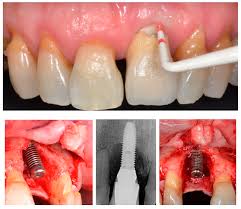

Peri-implant Disease

From The Blog of the Campbell Academy. – a routine “must read”.

“….It is absolutely crystal clear the patients who attend for routine maintenance get very little amounts of Peri-implant disease and the disease that they get is hugely treatable.

Whereas it is also absolutely clear that if they don’t attend the incidents of Peri-implant disease goes through the roof.

The number of dental implants placed in the United Kingdom over the last 10 years has rocketed and so here it comes.

Throughout that time there have been countless practitioners who have paid no attention to the fact that we have known for years that maintenance is the key to the reduction in Peri-implant disease…

….Peri-implant disease is a real reality even in the practices of people who do it properly, but for those who don’t it will be a disastrous long-term complication.”